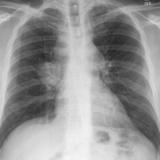

Lung Cancer

Nodules & Masses

Album: Nodules & Masses

Date: 01/25/2006

Size: 37 items

Views: 60060